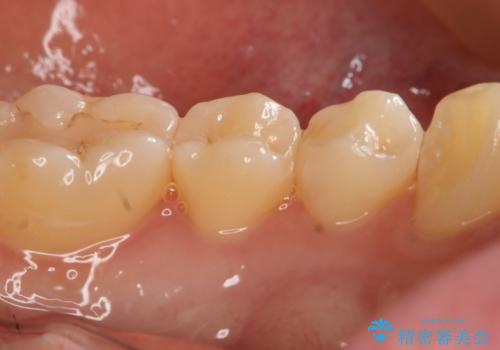

- 左下4番のう蝕を指摘され治療を希望された患者様です。

切削量などを考慮しクラウンでの治療を提案したところ、セラミックを希望されたのでフルジルコニアクラウンでの治療を選択しました。

う蝕が深かったので痛みが出る可能性をお伝えしましたが特に症状は現れなかったので、予定通りセラミッククラウンでの治療を行いました。